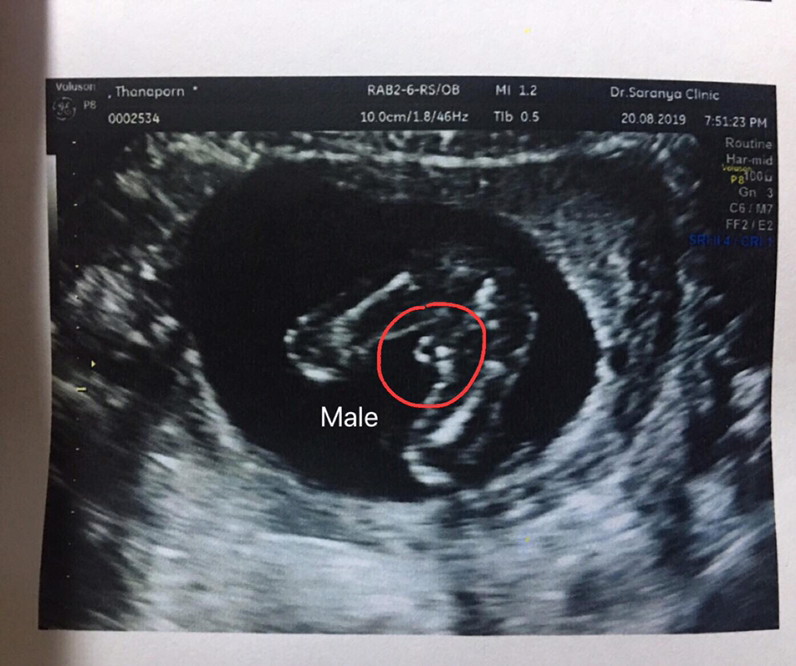

จู๋เด่นมาเลยค่ะแม่

แท่งจ้ะ โด่เด่มาก😂

กระจู๋ผมใหญ่คับ😂😂

เจ้าหำน้อยของแม่ 🤗

โด่ชัดเจนมากคร้า555